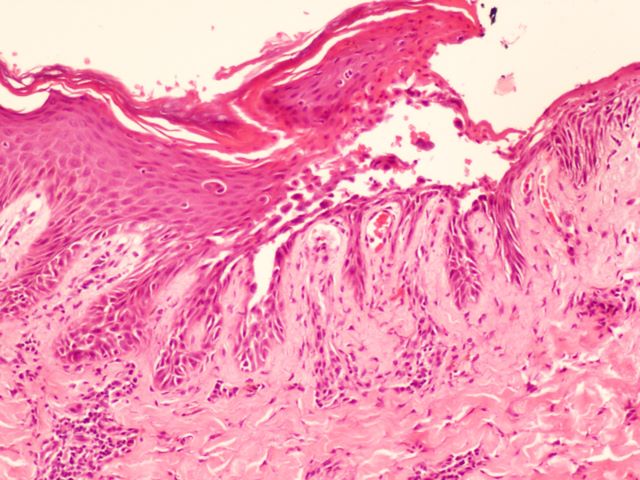

359 -- pb190054.jpg